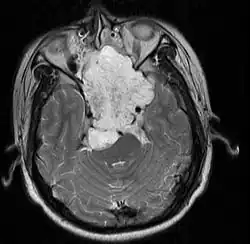

Duży struniak wychodzący ze stoku kości potylicznej, rozrastający się w kierunku pnia mózgu[1]

W MRI guz jest hipointensywny (sekwencja T1) lub hiperintensywny (T2), w TK hipodensyjny.